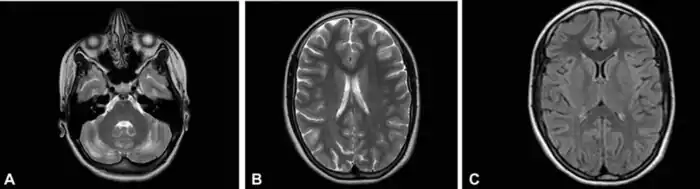

Иллюстрации